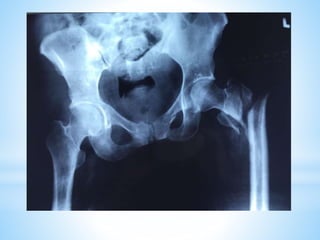

This document discusses the treatment of intertrochanteric hip fractures with different fixation devices. It notes that cephalomedullary devices are preferable to dynamic hip screws for fractures with posteromedial comminution or subtrochanteric extension due to their ability to provide controlled collapse and reduce bending forces. The document emphasizes the importance of pre-operative planning, proper reduction techniques, and achieving a tip-apex distance under 25mm for successful fixation with cephalomedullary devices.